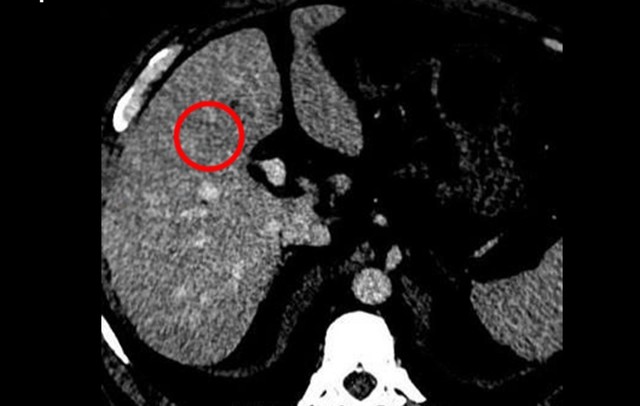

Kết quả chụp CT cho thấy gan xuất hiện khối tổn thương kích thước khoảng 22 x 24 mm cùng một số nốt nhỏ khác. Sinh thiết sau đó xác nhận ông mắc Ung thư gan giai đoạn sớm.

Kết quả CT cho thấy tổn thương gan (khoanh tròn). Ảnh: BVCC